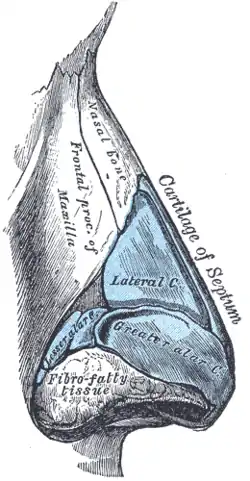

G. The cartilaginous pyramid of the nose

The cartilaginous septum (septum nasi) extends from the nasal bones in the midline (above) to the bony septum in the midline (posteriorly), then down along the bony floor. The septum is quadrangular; the upper half is flanked by two triangular-to-trapezoidal cartilages: the upper lateral-cartilages, which are fused to the dorsal septum in the midline, and laterally attached, with loose ligaments, to the bony margin of the pyriform (pear-shaped) aperture, while the inferior ends of the upper lateral-cartilages are free (unattached). The internal area (angle), formed by the septum and upper lateral-cartilage, constitutes the internal valve of the nose; the sesamoid cartilages are adjacent to the upper lateral-cartilages in the fibroareolar connective tissue.

Beneath the upper lateral-cartilages lay the lower lateral-cartilages; the paired lower lateral-cartilages swing outwards, from medial attachments, to the caudal septum in the midline (the medial crura) to an intermediate crus (shank) area. Finally, the lower lateral-cartilages flare outwards, above and to the side (superolaterally), as the lateral crura; these cartilages are mobile, unlike the upper lateral cartilages. Furthermore, some persons present anatomical evidence of nasal scrolling—i.e., an outward curving of the lower borders of the upper lateral-cartilages, and an inward curving of the cephalic borders of the alar cartilages.

External nasal anatomy

The form of the nasal subunits—the dorsum, the sidewalls, the lobule, the soft triangles, the alae, and the columella—are configured differently, according to the race and the ethnic group of the patient, thus the nasal physiognomies denominated as: African, platyrrhine (flat, wide nose); Asiatic, subplatyrrhine (low, wide nose); Caucasian, leptorrhine (narrow nose); and Hispanic, paraleptorrhine (narrow-sided nose). The respective external nasal valve of each nose is variably dependent upon the size, shape, and strength of the lower lateral cartilage.[22]